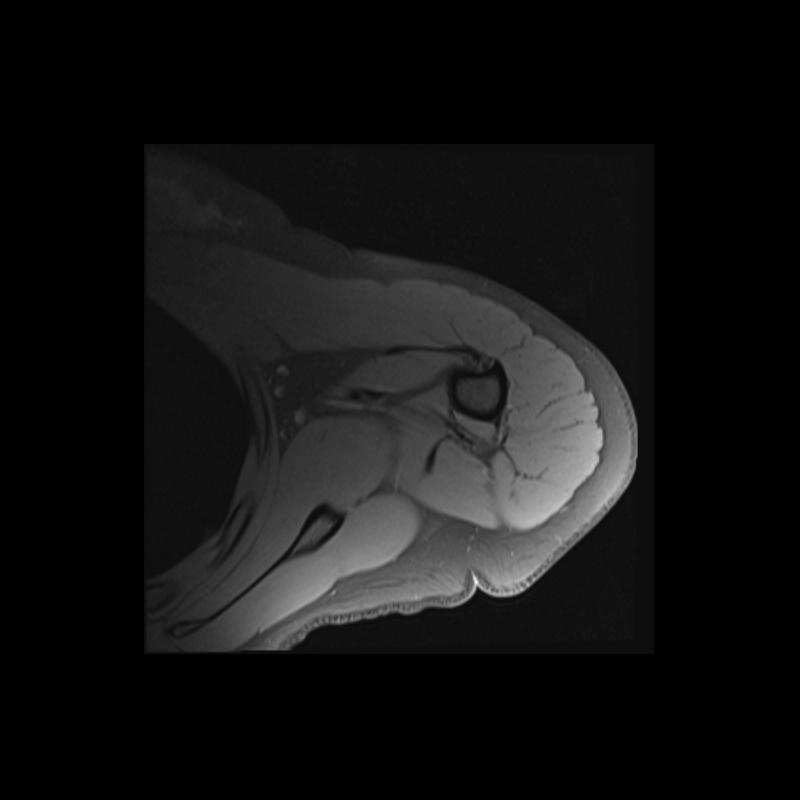

Shoulder MRI Anatomy